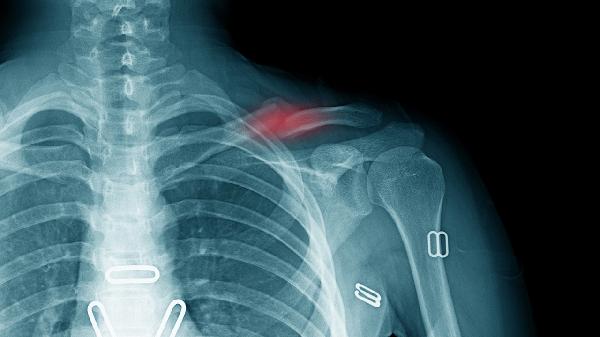

合并臂丛神经压迫症状是手术绝对指征。骨折端尖锐骨片可能刺伤锁骨下血管或臂丛神经,表现为上肢麻木、肌力下降。保守治疗无法解除机械压迫,需急诊手术探查减压,避免永久性神经损伤。

开放性骨折或局部皮肤张力过高时禁忌保守治疗。骨折端顶起皮肤可能造成局部坏死,增加感染风险。对于皮肤菲薄老年人或糖尿病患,需评估软组织覆盖情况,必要时选择内固定减少压迫。